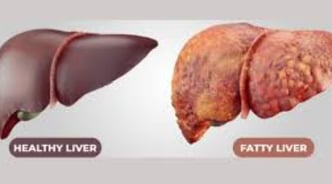

مرض الكبد الدهني، المعروف أيضًا باسم مرض الكبد الدهني غير الكحولي (NAFLD)، يتضمن تراكم الدهون الزائدة في الكبد.

يتميز مرض الكبد الدهني بوجود فائض من الدهون في الكبد، حيث تعتبر الاضطرابات الأيضية والاستهلاك المفرط للكحول من عوامل الخطر الرئيسية.

بينما قد لا يسبب تراكم الدهون مشاكل في البداية، إلا أنه يمكن أن يؤدي في النهاية إلى تلف الكبد.

مع مرور الوقت، يجعل هذا التراكم من الصعب بشكل متزايد على الكبد أن يعمل بشكل صحيح.

هناك نوعان رئيسيان من الكبد الدهني: مرض الكبد الدهني غير الكحولي (NAFLD) الذي يتضمن تراكم الدهون في الكبد، ومرض التهاب الكبد الدهني غير الكحولي (NASH) الذي يترافق مع علامات الالتهاب وتلف خلايا الكبد.

تليف الكبد: حيث يتم استبدال الأنسجة السليمة بنسيج ندبي.